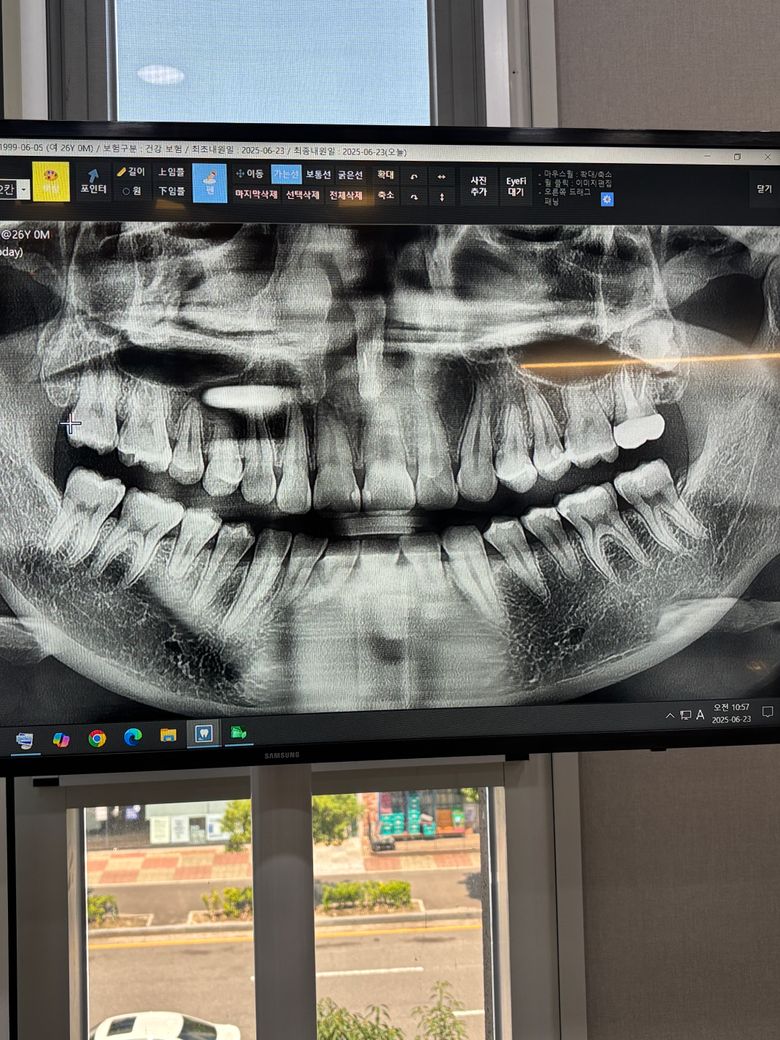

사랑니가 이렇게 난 경우 발치할 때 고통이 심할까요?

사진상 오른쪽 위에 사랑니가 사진처럼 나서 신경이 너무 아퍼서 병원에 갔더니 대학병원 가서 발치를 하라고 합니다.

• 1번 째 사진

저위치에 잇는 사랑니는 특별한 이유가 없다면 발치를 하실필요는 없습니다. 만약 발치를 하게된다면 수면마취는 하지 않고 사랑니 전문 병원에서 발치는 가능할것같습니다.

사진상 오른쪽 위(실제로 왼쪽 위) 위치가 좀 깊네요 신경과는 큰 상관없으나 대학병원 구강외과 가보시는 것을 추천합니다.수면마취까지는 안해도 됩니다.